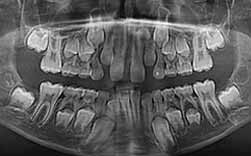

Uma radiografia panorâmica conduzirá ao diagnóstico e ajudará a orientar a conduta terapêutica na infância.